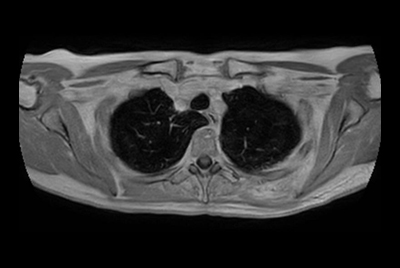

Contrast-free renal imaging